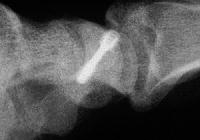

Xray before

Click for larger image